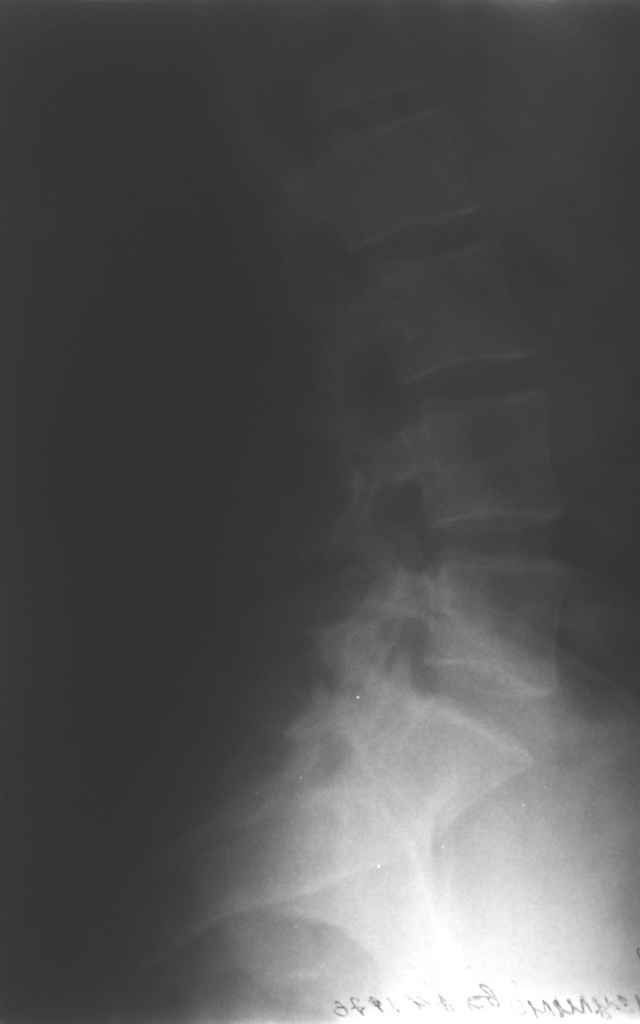

13/03/03 |  13/03/03 |  13/03/03 |  15/09/06 |  15/09/06 |  07/03/07 |  07/03/07 |  19/12/06 | К нам в клинику поступила пациентка 30 лет с диагнозом: Постравматическая ротационная стабильная деформация тазового кольца. Относительное укорочение левой н\конечности на 1 см. Левосторонний компенсаторный сколиоз 2 ст. Болевой синдром. травма автодорожная в январе 2003г. Пассажирка переднего сидения ваз 2109. лечились положением по Волковичу. С марта 2003 года жалуется на боли в тазу, ппояснице усиливающиеся при движении.В настоящее время жалобы на боли в области крестца, КПС больше слева, в пояснично-крестцовом отделе позвоночника. неприятные ощущения, щелчок при выпрямлении правого тазобедренного сустава из положения полного сгибания. боли в тазу появляются при ходьбе ч\з 100 м, так же при вставании из положения сидя, после сидения в течении 2-3 часов. при ходьбе более 100 м появпяется зябкость стоп больше справа. ходит при помощи трости в правой или в левой руке. без трости боли появляются сразу после начала ходьбы. пальпация болезненна в паравертебральных точках средне-грудного и пояснично-крестцового отделов позвоночника, КПС с обеих сторон. Объем движений в тазобедренных суставах полный.правый КПС заблокирован. симптомы натяжения с обеих сторон отрицательны.С 2003г. лечится консервативно, получала ЛФК, массаж, физиолечение - без эффекта. в 2005г. лечилась в санатории с ортопедическим уклоном, получала плавание в минеральной воде, магнитотерапия, массаж, ЛФК. отмечала умеренное улучшение в течении 2 недель.Вопросы:надо ли оперировать, т.е. устранять относительное укорочение левой н\конечности и как?Если не оперировать, то как лечить консервативно?Р-граммы, КТ прилогаются.

Проблема Вашей пациентки находится на границе интересов специальностей ортопедия (вертебралогия) и неврология (нейрохирургия), вероятно, поэтому так мало откликов на ваше обращение. Представленные рентгенограммы не все информативны (особенно спондилограммы от сентября 2006 года). Вероятно, необходимы дополнительные методы исследования к.т. МТГ, ЯМРТ, миелография.

просьбе. досылаю КТ, фуккциональные Р-граммы пояснично-крестцового отдела позвоночника, фото пациентки.

Здравствуйте уважаемые коллеги. Высылаю обещаннное ЯМРТ. Никаких нарушений м\позвонковых дисков, мяггкотканных образований на уровне Th12-S3 не обнаружено.